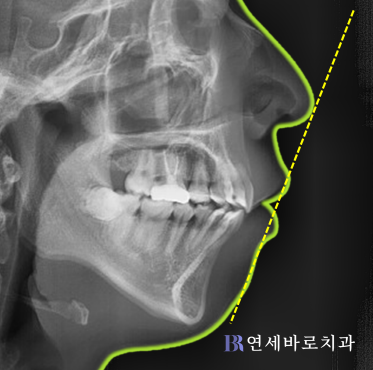

무턱에 의한 돌출입 양상을 보이며,

입을 다물 때 입술 주변의 근육이

긴장되어 있음을 알 수 있습니다.

무턱 돌출입의 전형적 특징인

과개교합 양상이 관찰됩니다.

(과개교합은 윗니가 아랫니를

깊게 덮는 현상을 의미합니다.)

치아 배열이 심하게 좋지 않아서

치아를 발치하지 않은 상태로

무리하게 교정을 강행할 경우

입이 더 돌출될 수도 있습니다.

(아랫니가 윗니보다 뒤에 있어서

상악 치열이 더 나와 보임)